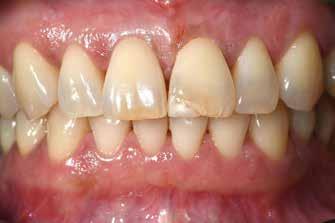

ezen a területen, a fogászat profitál az ilyen fejlesztésekből, és ma már számos kezelési megoldást kínálunk pácienseinknek. Rezidens korom alatt klinikai szakfelügyelőként dolgoztam akadémiai környezetben, ahol elsősorban kivehető fogpótlásra szoruló geriátriai betegeket kezeltem, valamint olyanokat, akiknek fix fogpótlásra, például fog- vagy implantátummal ellátott hagyományos rögzített fogpótlásra (azaz korona és híd) volt szükségük, elsősorban arany vagy fémkerámia felhasználásával. Az ezekben az években megfigyelt klinikai kudarcok és a beavatkozások invazív jellege, nevezetesen a foghúzásra vonatkozó több fúrás és egyszerűbb döntések jelentős szerepet játszottak a kutatási irányvonalam kialakításában az évek során. Ez volt az az időszak is, amikor elkezdtem többet foglalkozni az adhezív fogászattal, ami megváltoztatta a protetikai fogászat klasszikus arculatát, és határozottan kevésbé invazívvá tette azt (1. a-d ábrák). Ma, az intenzív transzlációs és klinikai kutatás eredményeként, különös tekintettel a fogászati bioanyagok alkalmazására, klinikai szakértelmem a minimálisan invazív, adhezív eljárások alkalmazására összpontosít a protetikai fogászatban, a szövődmények kezelésére és a költséghatékony kezelési lehetőségek felkínálására.

Lényegében az adhezív fogászat szűkítette a fogszabályozás és a helyreállító fogászat közötti határfelületet, ezért a fogszabályozás tudományágat rekonstrukciós fogászatnak nevezik. Minden kutatási és klinikai erőfeszítésem arra irányul, hogy minden rendelkezésre álló fogászati kemény- és lágyszövetet megmentsek, elkerüljem a foghúzásokat, megelőző intézkedéseket gyakoroljak, és növeljem a fogászati rekonstrukciók hosszú távú tartósságát, miközben új bioanyagokat fejlesztek ki.

A beavatkozás tekintetében –részben a betegek igényei miatt – a megközelítések a kivehető helyett a rögzített rekonstrukciók, az esztétikusabb megoldások és – ahol lehetséges – a fémmentes rekonstrukciók felé mozdultak el.